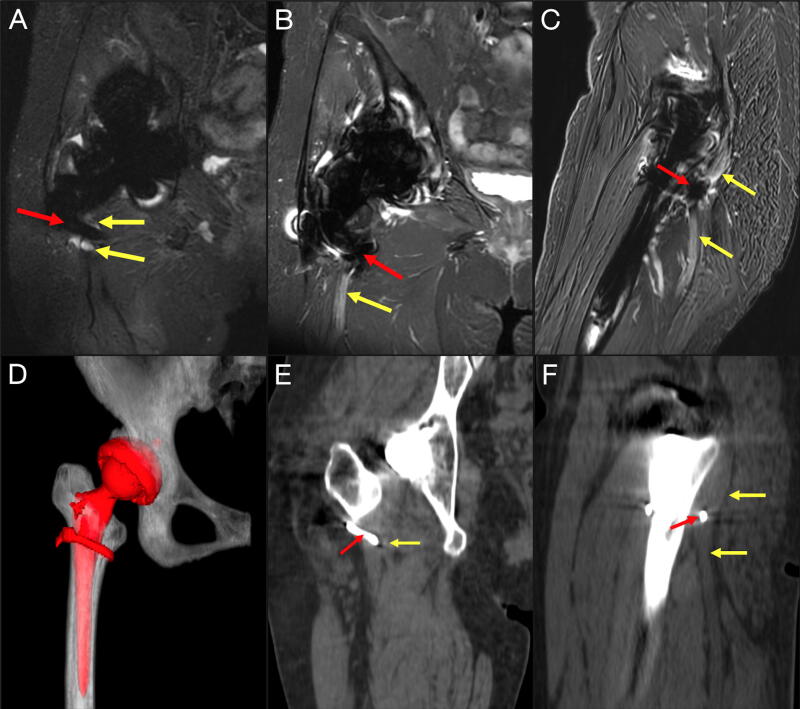

与全髋关节置换术(THA)相关的坐骨神经损伤会导致慢性和进行性残疾。损伤的机制多种多样,管理上的细微差别往往因人而异。我们讨论了一例因先前的全髋关节置换术(THA)造成的股骨环扎钢丝引起的桑德兰4型坐骨神经横断,以强调处理复杂病例时的最佳临床策略。一位 65 岁的女性因同侧髋关节置换术后 1 年开始出现的右坐骨神经感觉运动神经病变恶化、药物难治而来到神经外科门诊就诊。神经系统检查发现她的踝关节背屈/跖屈和足内翻/外翻无力(运动量表 2-3/5)、足趾伸展/屈曲无力(1/5)、足部麻木和过度紧张。肌电图证实了坐骨神经病变。磁共振神经图(MRN)显示,右侧坐骨神经增粗,与股骨环扎线相连,在重建的计算机断层扫描成像中显示为连续的。术中发现,该钢丝明显横断并留在坐骨神经内,需要骨科会诊并在横断处剪断钢丝。切除了周围的神经瘤,并使用神经异体移植插管重建了缺损。术中神经电生理监测(IONM)信号保持稳定。X光片证实钢丝断开过程并不复杂。患者第二天就出院回家了,随访1个月后症状明显缓解。股骨卡环钢丝导致坐骨神经横断并持续神经压迫的延迟病例非常罕见。损伤的解剖结构可能是高风险的,这就要求在 THA 和神经成形术病例中制定周密的手术计划。策略包括术前 MRN 评估神经损伤的病理解剖、神经外科和矫形外科联合管理以及多模式 IONM,以降低术中神经损伤的风险并优化预后。

Sciatic nerve injury associated with total hip arthroplasty (THA) confers chronic and progressive disability. Mechanisms of injury are heterogeneous and management nuances are often case-specific. We discuss a Sunderland Type 4 sciatic nerve transection by femoral cerclage wire from prior THA to highlight optimal clinical strategies when approaching complex cases. A 65-year-old woman presented to the neurosurgery clinic with worsening, medically refractory right sciatic sensorimotor neuropathy that began 1 year after ipsilateral hip arthroplasty. Neurological examination detected weakness in ankle dorsiflexion/plantarflexion and foot inversion/eversion (motor scale 2-3/5), toe extension/flexion (1/5), foot numbness, and hyperesthesia. Electromyogram confirmed sciatic neuropathy. Magnetic resonance neurogram (MRN) showed a thickened right sciatic nerve abutting a femoral cerclage wire, which appeared contiguous on reconstructed computed tomography imaging. Intraoperatively, the wire was discovered to have clearly transected and remained lodged within the sciatic nerve, requiring orthopedic surgery consultation and wire cutdown at the transection site. The surrounding neuroma was excised and the defect was reconstructed using nerve allograft interposition. Intraoperative neurophysiology monitoring (IONM) signals remained stable. Radiographs confirmed uncomplicated wire disconnection. The patient was discharged home the next day and reported significant symptomatic relief at 1-month follow-up. Delayed presentation of sciatic nerve transection by femoral cerclage wire with ongoing neural compression is rare. The anatomy of injury can be high risk, impelling thoughtful operative planning in THA as well as neuroplasty cases. Strategies include preoperative MRN to evaluate the pathoanatomy of nerve injury, neurosurgery and orthopedic surgery comanagement, and multimodal IONM to reduce risks of intraoperative neural injury and optimize outcomes.